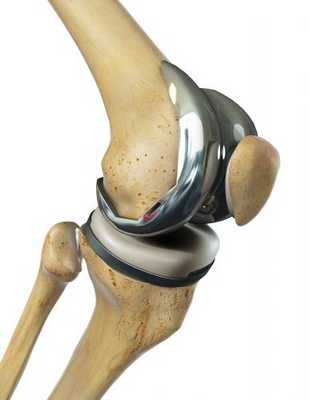

Эндопротезы коленного сустава предназначены для замены естественных компонентов при сильном артрозе. При этом часть кострукции покрывает конец бедренной кости. Другая часть закрывает область голени. Искусственные скользящие поверхности для производства которых используются металл и полиэтилен восстанавливают подвижность в колене. Благодаря этому после артроза пациент может двигаться как раньше.© Gelenk-Klinik

Тотальный эндопротез коленного сустава — это замена разрушенных вследствие артроза элементов на искусственные. По причине чрезмерных нагрузок из-за массы тела, а также из-за травм либо воспалений, коленные суставы чаще других подвергаются износу. Частичные эндопротезы заменяют только часть коленного сустава при незначительных травмах, а тотальные предназначены для полной их замены.

Единственная тактика лечения, которая дает результаты - эндопротезирование. Индустрия выпускает модернизированные имплантаты под требования любого пациента. Искусственные конструкции создаются из биосовместимых материалов, представленных керамикой, инновационными сплавами металлов и высокомолекулярным полиэтиленом, которые не оказывают токсического, аллергического и канцерогенного воздействия на окружающие структуры.

Самый распространенный тип импланта коленного сустава.